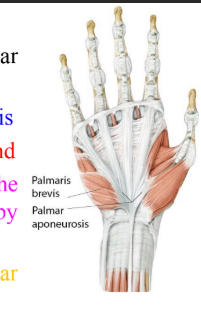

Palmaris brevis

Palmaris brevis | Flexor retinaculum and palmar aponeurosis | Skin along medial border of hand | Helps with gripping | Superficial branch of ulnar nerve |